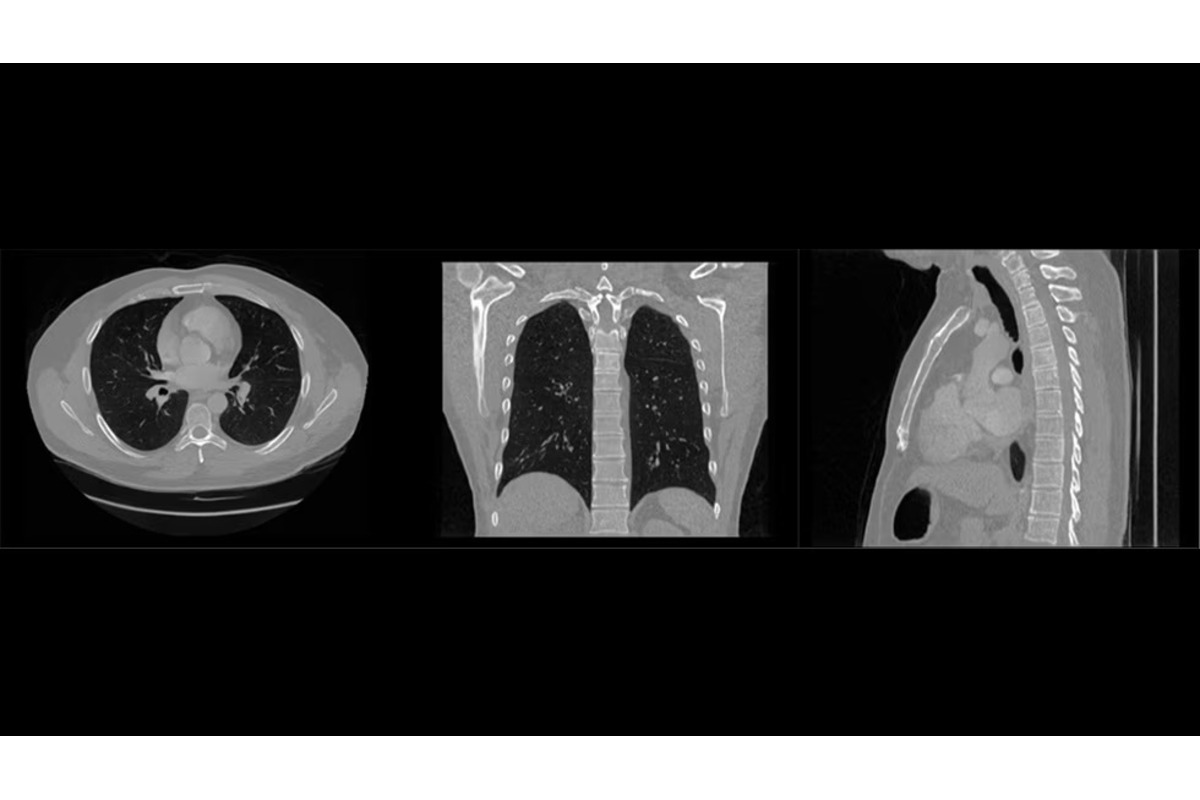

Philips is exploring the use of synthetic medical imaging to enhance AI development in healthcare while maintaining patient privacy. Traditional AI training relies on real-world medical data, which is often fragmented and restricted due to privacy and sharing challenges. To overcome these barriers, Philips is generating realistic synthetic CT and MRI scans that mimic the diversity of real-world data without exposing patient information.

As a key contributor to Project SEARCH a collaborative initiative to advance diagnostic AI through synthetic data Philips is developing algorithmically generated datasets designed to be both technically accurate and clinically meaningful. These datasets help train AI systems to detect diseases earlier, improve diagnostic precision, and strengthen clinical decision-making, particularly in oncology and cardiovascular care.

By integrating synthetic data into AI workflows, Philips aims to fill data gaps, reduce model development time, and improve algorithm reliability, all while safeguarding sensitive health information. The company is also working with clinical partners to establish validation frameworks that ensure the quality, privacy, and relevance of synthetic images. This initiative underscores Philips’ commitment to advancing responsible, people-centered AI fostering innovation that enhances clinician trust, supports healthcare providers, and contributes to better patient outcomes.